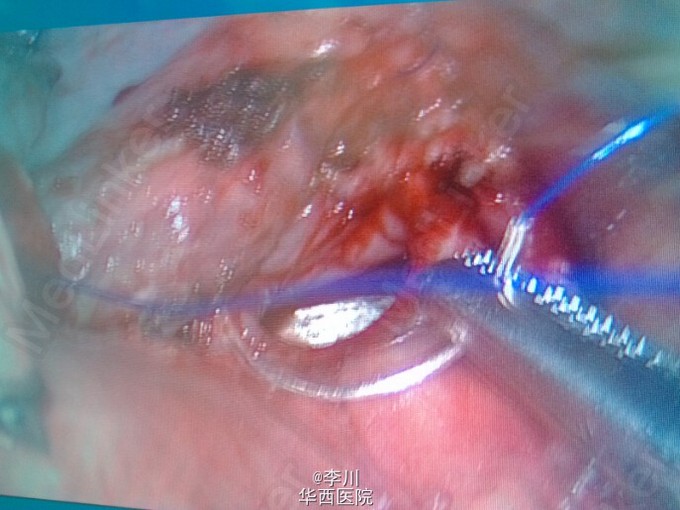

大医院技术更好?---右上肺鳞癌伴肺不张一例

患者为50岁男性,因咳嗽咳痰、痰中带血3+月入院。3+月前患者因上述症状于当地医院就诊,行相关检查后诊断为右肺上叶鳞癌。却被告知不能手术,只能放化疗。患者不甘心,遂于我院就诊,经我院知名专家详细读片评估后,认为有手术指证,首选手术治疗。查体心腹无特殊异常。右上肺呼吸音弱,未闻及干湿罗音,左肺呼吸音无明显异常。